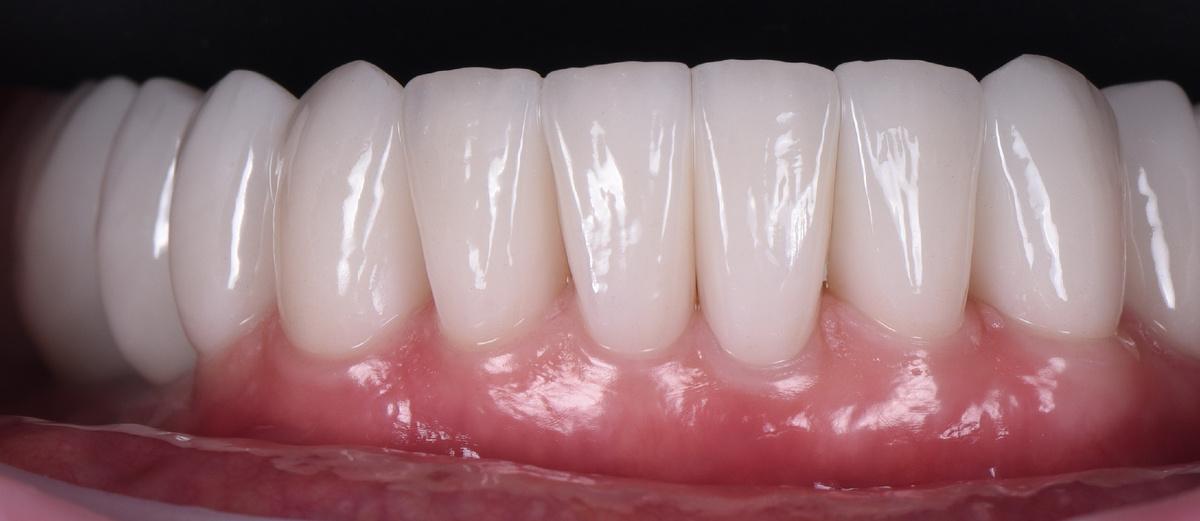

Следующий шаг — коронки на нижние зубы:

Завершающий этап — после протезирования на имплантатах на нижней челюсти слева, в той области, где костная ткань восстанавливалась дольше всего